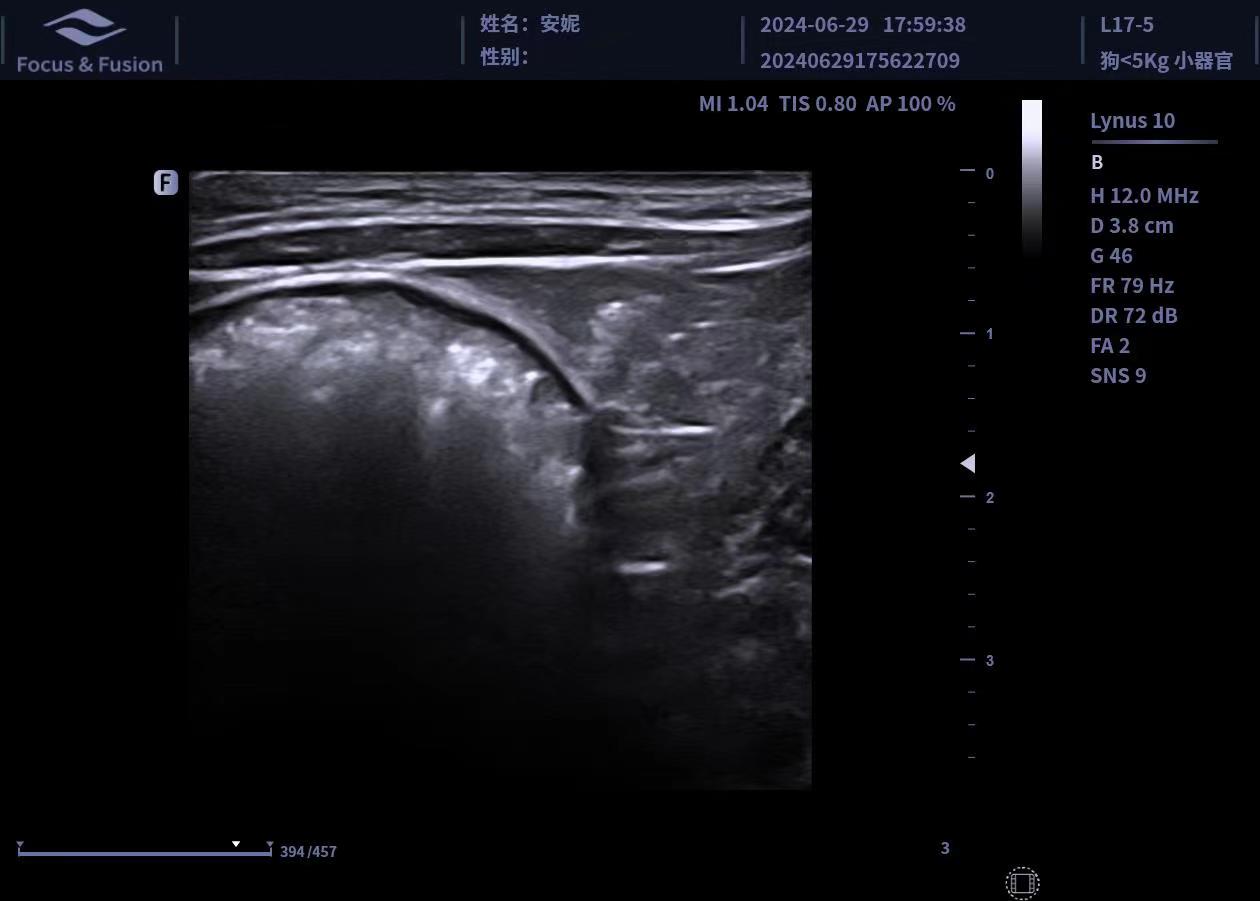

圖片展示

Image List